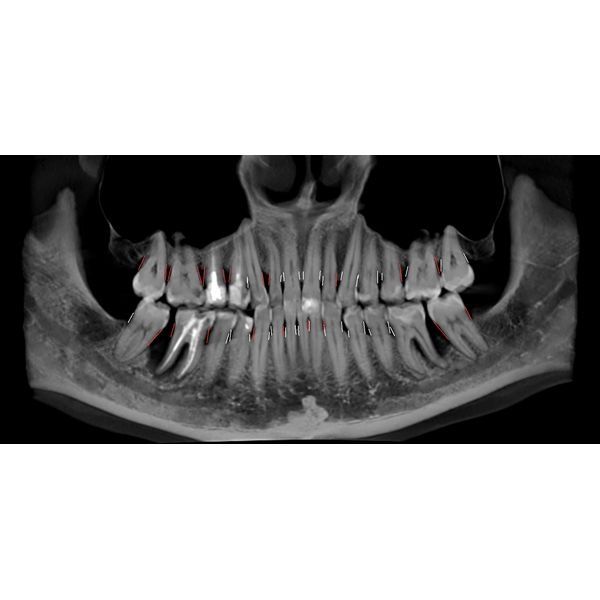

Провели компьютерную томографию — КЛКТ, т. е. 3D-рентген обеих челюстей: выявили неравномерную деструкцию костной ткани в области жевательной группы зубов нижней челюсти до 2/3 длины корня зуба, в области остальных зубов — до 1/3 длины корня.

На пародонтограмме (графическом изображении всех зубов с каждой стороны) визуализировались глубокие пародонтальные карманы в области жевательных зубов нижней челюсти и множественные пародонтальные карманы в области всех зубов верхней челюсти.